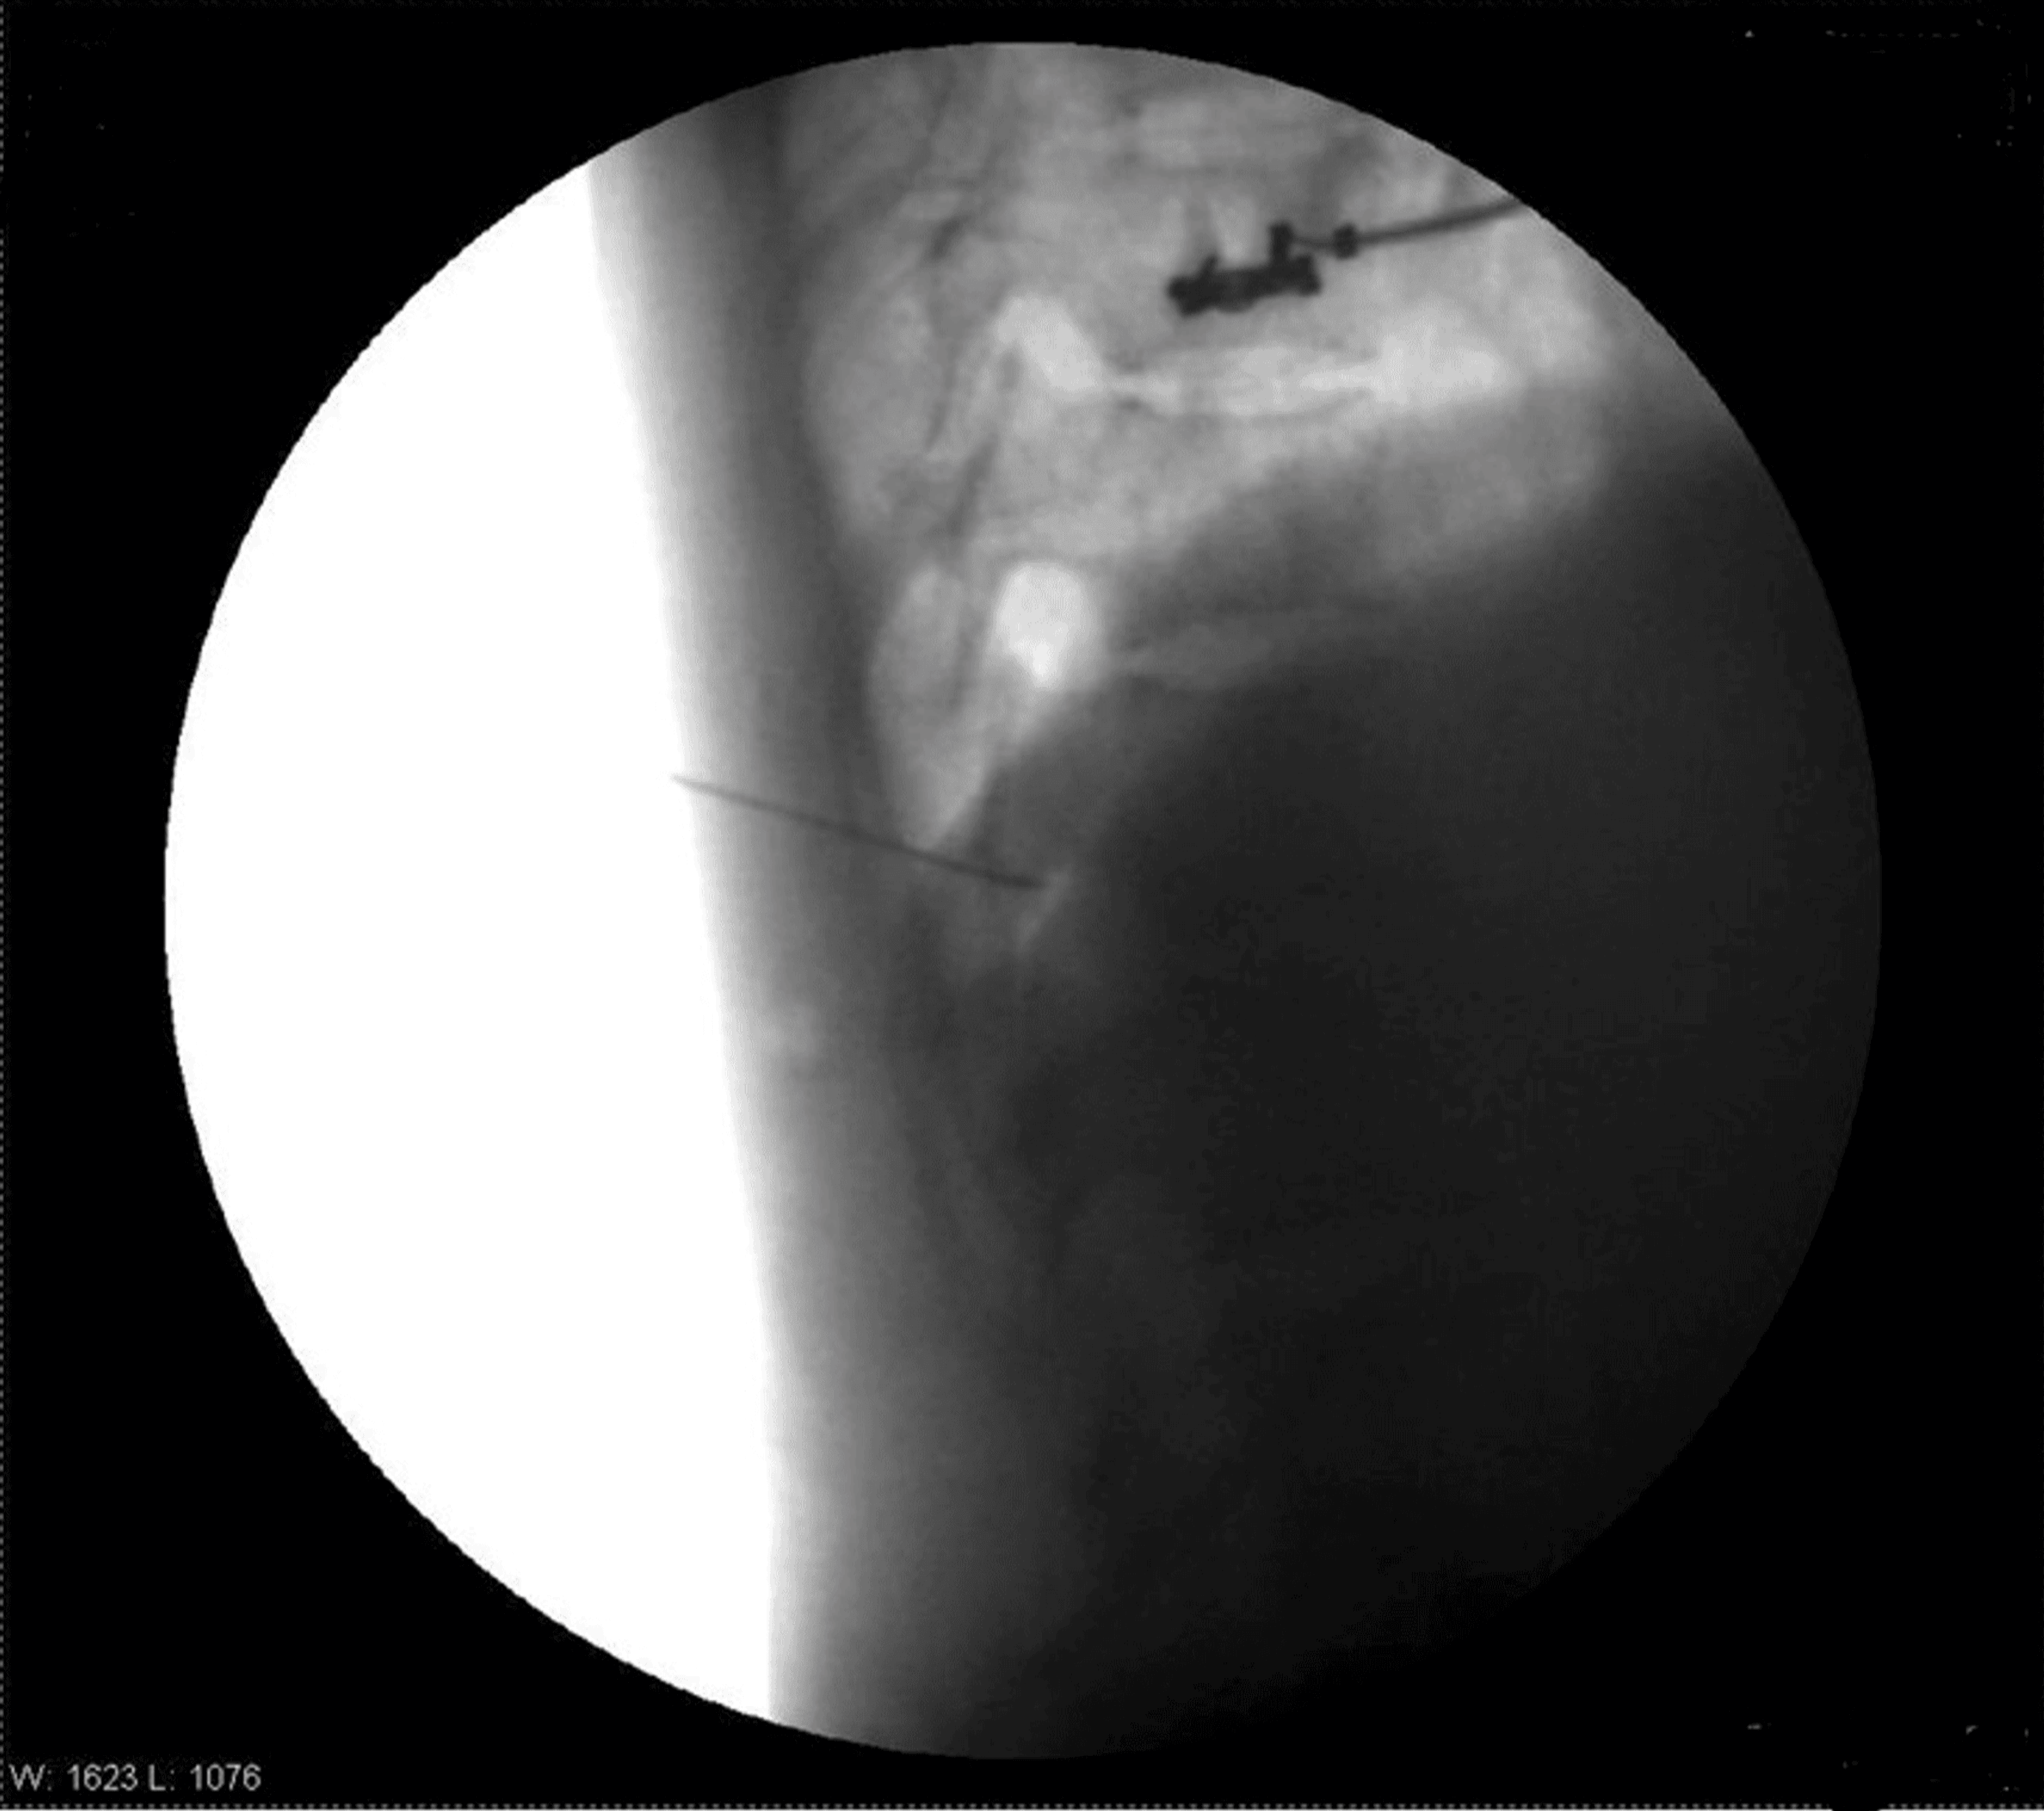

The patient was positioned prone. After painting and draping, the transverse process of T8 was located on the right side with the help of a C-arm. A Quincke needle (22 G) was inserted under fluoroscopic guidance to reach the transverse process of T8. The needle tip was advanced caudally along the transverse process until a loss of resistance was felt. The needle’s position was confirmed via fluoroscopy by injecting iohexol 300 radiocontrast dye, with images obtained in both anteroposterior and lateral views (Figures 1–4).

Four milliliters of levobupivacaine 0.5% were administered. Similar steps were performed for the T10 and T12 vertebrae. Sensory levels were assessed using hot and cold glass test tubes along the mid-axillary line. Motor blockade was evaluated using Snider’s match-blowing test, where the patient was asked to blow out a match held 15 cm from the mouth. Vitals after five minutes were HR of 90/min, BP of 100/68 mmHg, SpO2 of 98%, and RR of 14/min.